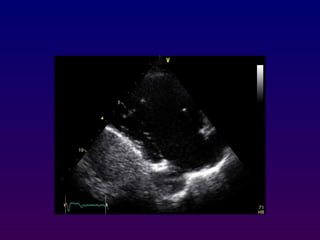

With the patient maintained in the left lateral

decubitus position, the transducer is placed near

In the apical four-chamber view, all four

chambers of the heart may be seen The left

ventricle appears as a truncated ellipse,RV

triangular with the interventricular septum, apex

formed by LV, and lateral walls visualized.

Apical four-chamber

With the patientmaintained in the left lateral decubitus position, the transducer is placed near the apex of the heart with an inferior orientation In the apical four-chamber view, all four chambers of the heart may be seen The left ventricle appears as a truncated ellipse,RV triangular with the interventricular septum, apex formed by LV, and lateral walls visualized. Apical four-chamber